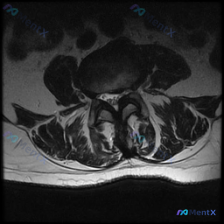

看到一张很典型的腰椎MRI轴位片,关于椎间盘病变的观察,整理了完整读片思路和分析,分享给大家。 病例影像基础信息 这是一张腰椎MRI的T2加权轴位图像,层面为腰椎间盘水平。 影像观察核心发现 1. 椎间盘结构:中心前方的椎间盘T2信号较正常髓核降低,呈灰黑色,提示椎间盘脱水退行性改变 2. 突出情况...

看到这张腰椎MRI-T2轴位影像,大家第一反应是什么?问题问的是椎间盘病变,整理一下分析思路和大家分享。 一、影像基本信息 这是腰椎椎间盘层面(最可能为L4/5或L5/S1)的T2轴位扫描,我们先梳理所有客观发现: 1. 椎间盘情况:中央区域信号较正常稍低,提示椎间盘脱水变性;但后缘形态完整,没有明...

刚整理完这份腰椎MRI轴位片的分析,整个思路挺典型的,分享给大家一起讨论。 病例基本影像信息 这是一份腰椎MRI的T2加权轴位(横断面)扫描,层面位于腰椎间盘层面,可观察到的结构包括:前方椎体后缘、中部椎管内含硬膜囊、双侧关节突关节、后方椎板棘突以及两侧背肌。 核心影像发现 1. 椎间盘改变:椎间盘...